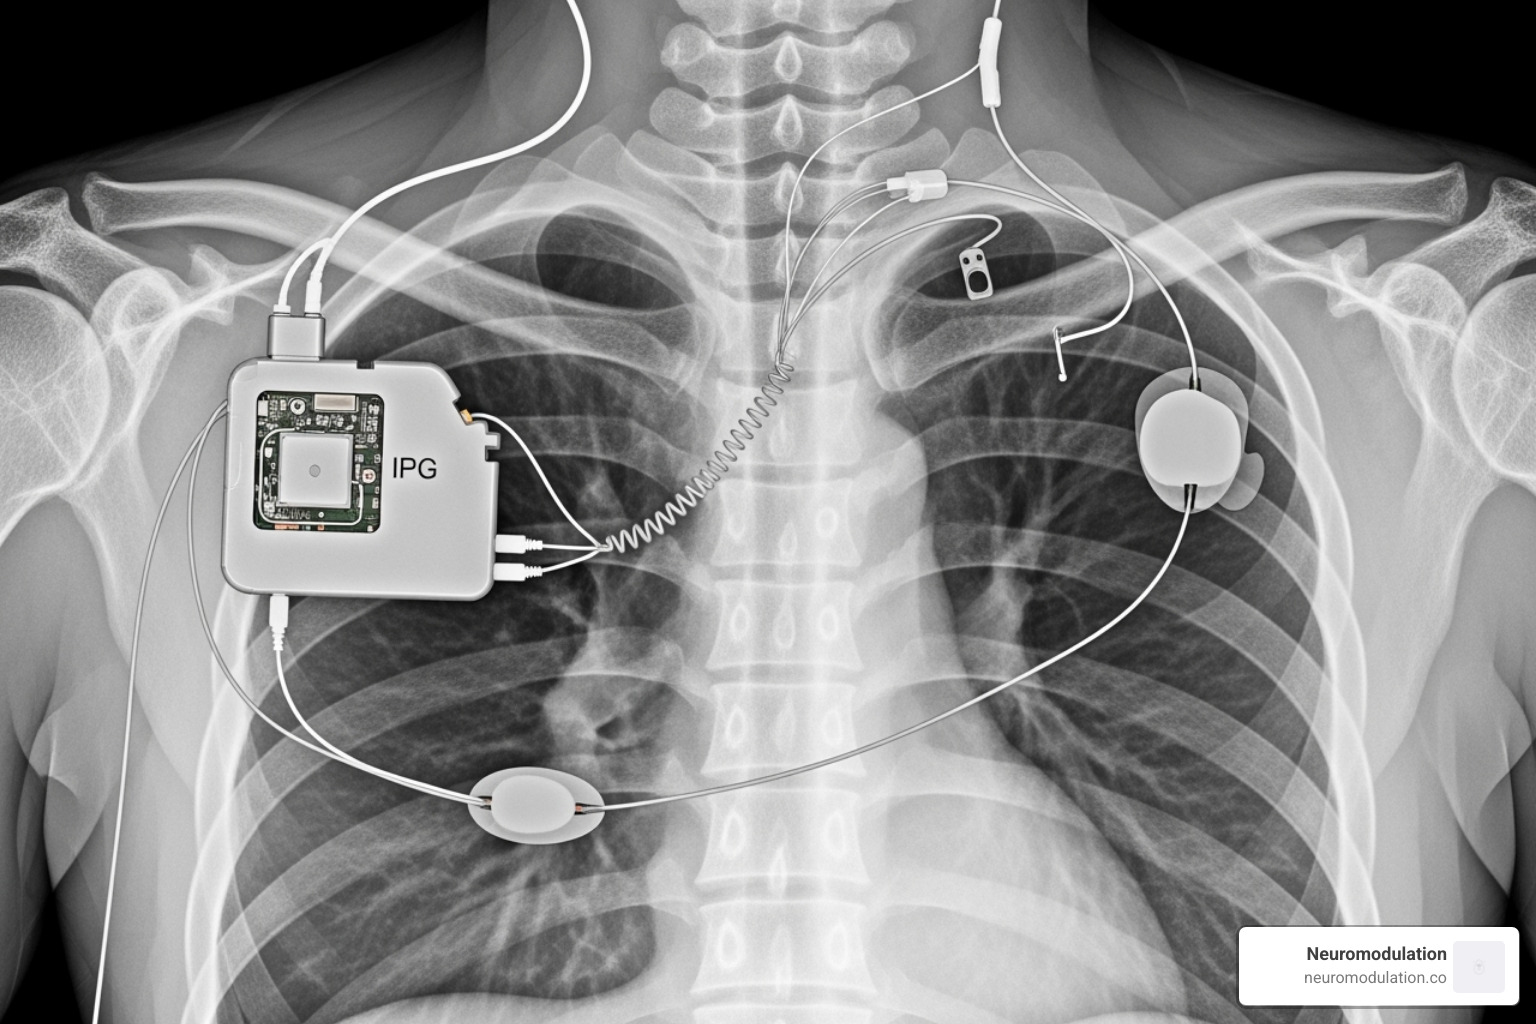

The system has three components: an implantable pulse generator (IPG) in the upper chest, a sensing lead between the chest muscles to monitor breathing, and a stimulation lead around the hypoglossal nerve. The evidence base is solid, with the STAR trial and ADHERE registry demonstrating consistent results.

The IPG and leads are often visible on perioperative imaging like chest X-rays. Beyond identification, these devices require special precautions.